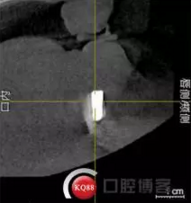

檢查:上頜無(wú)牙頜假牙穩(wěn)定性尚可,下頜3435364243殘根;33殘冠1-2度松動(dòng),其他牙齒缺失;CBCT檢查:下頜牙槽骨前牙區(qū)骨高度足,后牙區(qū)骨高度最低為8mm,骨寬度足。

1)術(shù)前檢查,拍攝臨床照片及CBCT檢查,制取活動(dòng)義齒參考模型,指導(dǎo)后期最終修復(fù)的牙齒排列

2)術(shù)前準(zhǔn)備及手術(shù)過(guò)程,測(cè)量血壓及血糖,簽種植知情同意書(shū);嚴(yán)格遵循無(wú)菌操作,局麻下采用微創(chuàng)技術(shù)于323436分別植入osstem4.0X10,4.0X10,4.5X7; 434446分別植入osstem4.0X1O,4.0X10,4.5X7.初期穩(wěn)定性均達(dá)到了35N.CM以上;嚴(yán)密縫合,止血,種植體位點(diǎn)和方向與設(shè)計(jì)一致。